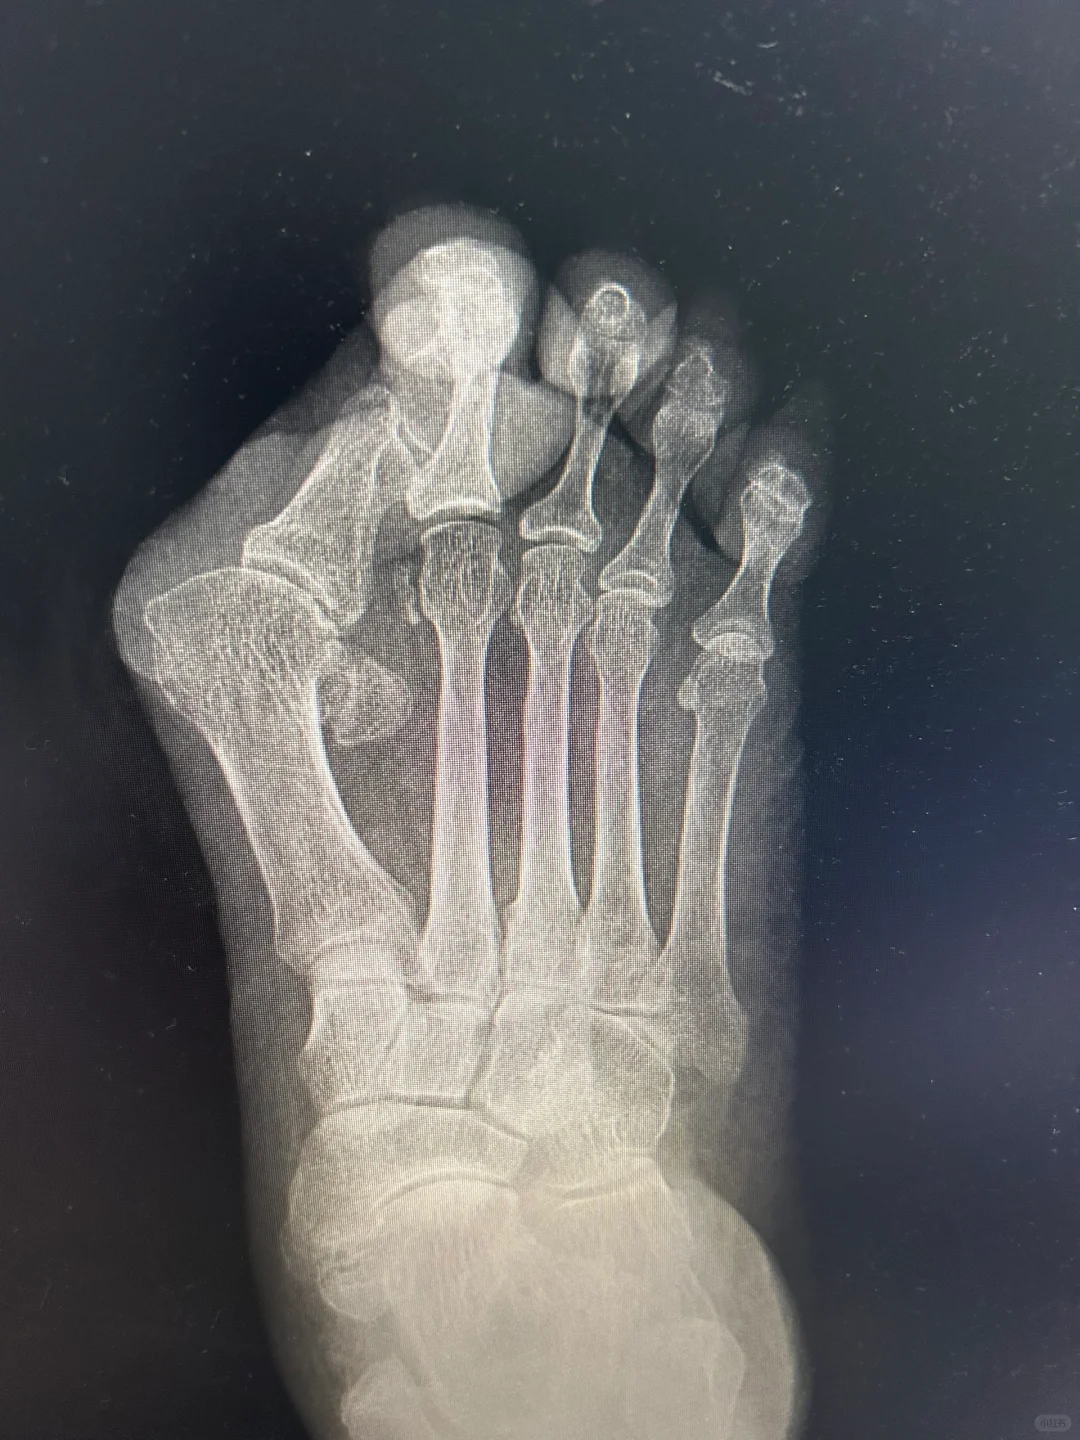

12年前的微创手术